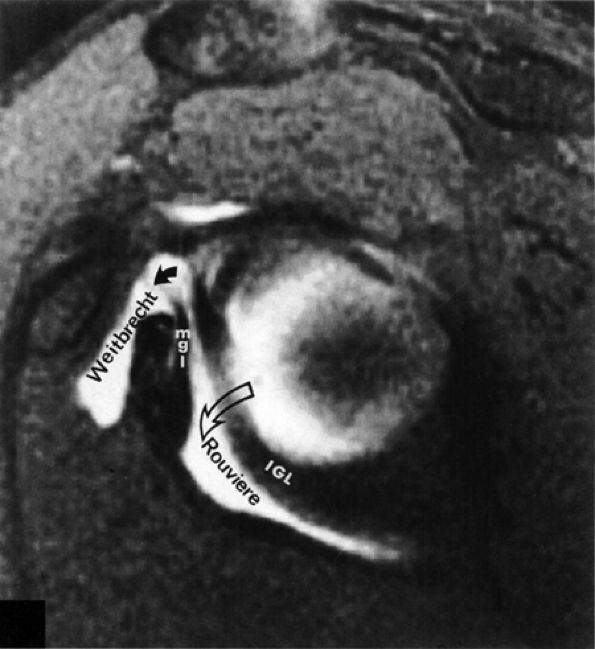

FIGURE 8.85 ● Normal foramen of Weitbrecht (solid curved arrow) is shown between the middle glenohumeral ligament (MGL) and the superior glenohumeral ligament. The foramen of Rouviere (open curved arrow) is located between the MGL and the inferior glenohumeral ligament (IGL).